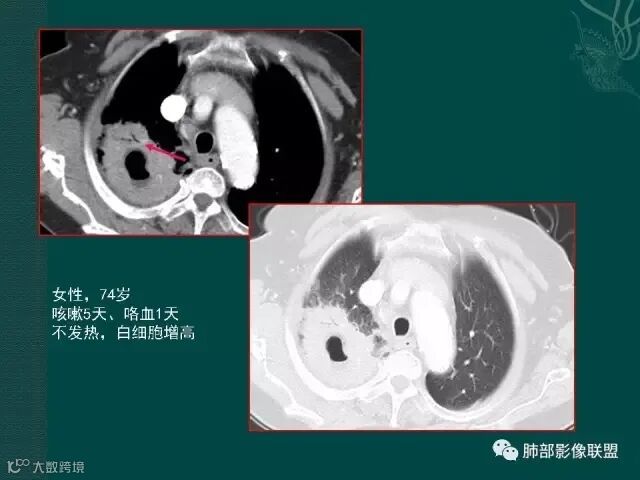

大片液化坏死,内多发空泡,初学者可能感觉是感染,但红箭头所指洞壁虽然不很厚,但仍可见到边界不清的低密度区,黄箭头所指病变侵犯胸膜。

定要记住,在免疫力低下,或白细胞降低的病人,如果在化疗过程中出现痰中带血,最大可能不是肿瘤进展,也不是侵犯血管,而是侵袭性的肺曲霉菌感染。

该病例进展较快,悬球征-霉菌感染的特异征象。